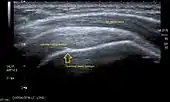

Transversal ultra sonography of the supraspinatus tendon